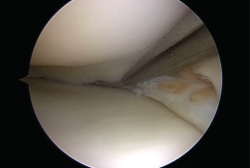

Figura 4. Asa de cubo: sutura con 3 puntos mediante técnica todo dentro.

Biomecánicamente, se ha demostrado que una configuración de sutura vertical ya sea dentro-fuera o técnicas todo dentro cada 3 a 5 mm proporciona superioridad sobre la configuración horizontal(10)(Figura 4).

Tanto técnicas dentro-fuera como todo dentro se ha informado que tienen tasas de curación, complicaciones y resultados funcionales similares(11).